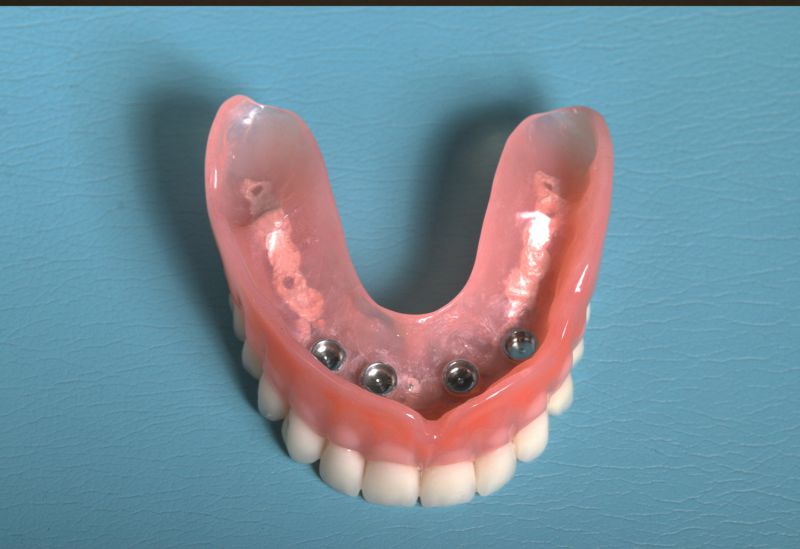

Samodzielna korona nie obciążająca zębów sąsiednich - to dzisiaj możliwe.

+ brak konieczności szlifowania zębów

+ brak zalegania resztek pokarmowych pod mostem

Wszczepienie implantu na ogół jest zabiegiem bezbolesnym i nie wymagającym dłuższej rekonwalescencji.